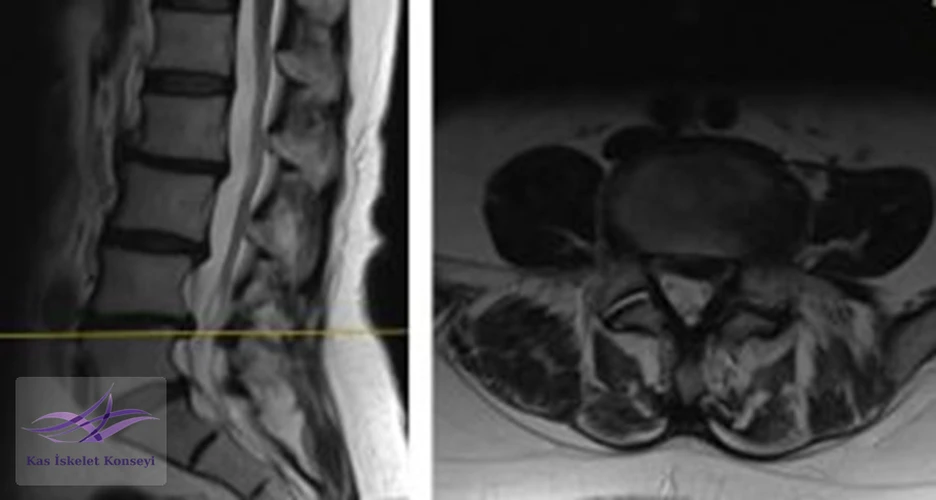

İncelemeler: Lomber MRG: L4-5 diskal bulging ve sol foraminal stenoz var. Kalça MRG istendi, iki yanlı trokanterik bursit rapor edildi.

Resim 1. Lomber MRG, L4-5 seviyesi median kesit.

Resim 2. Lomber MRG, L4-5 seviyesi sağ paramedian kesit.

Resim 3. Lomber MRG, L4-5 seviyesi sol paramedian kesit foramen stenozunu göstermekte.